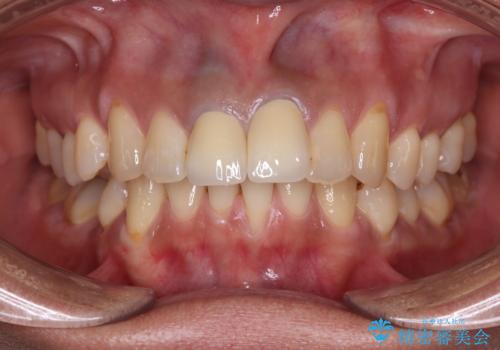

前歯の黒い縁が気になる オールセラミッククラウンで自然な口元に

オールセラミッククラウンは金属を使用していないため、本物の歯のような綺麗な仕上がりとなりました。